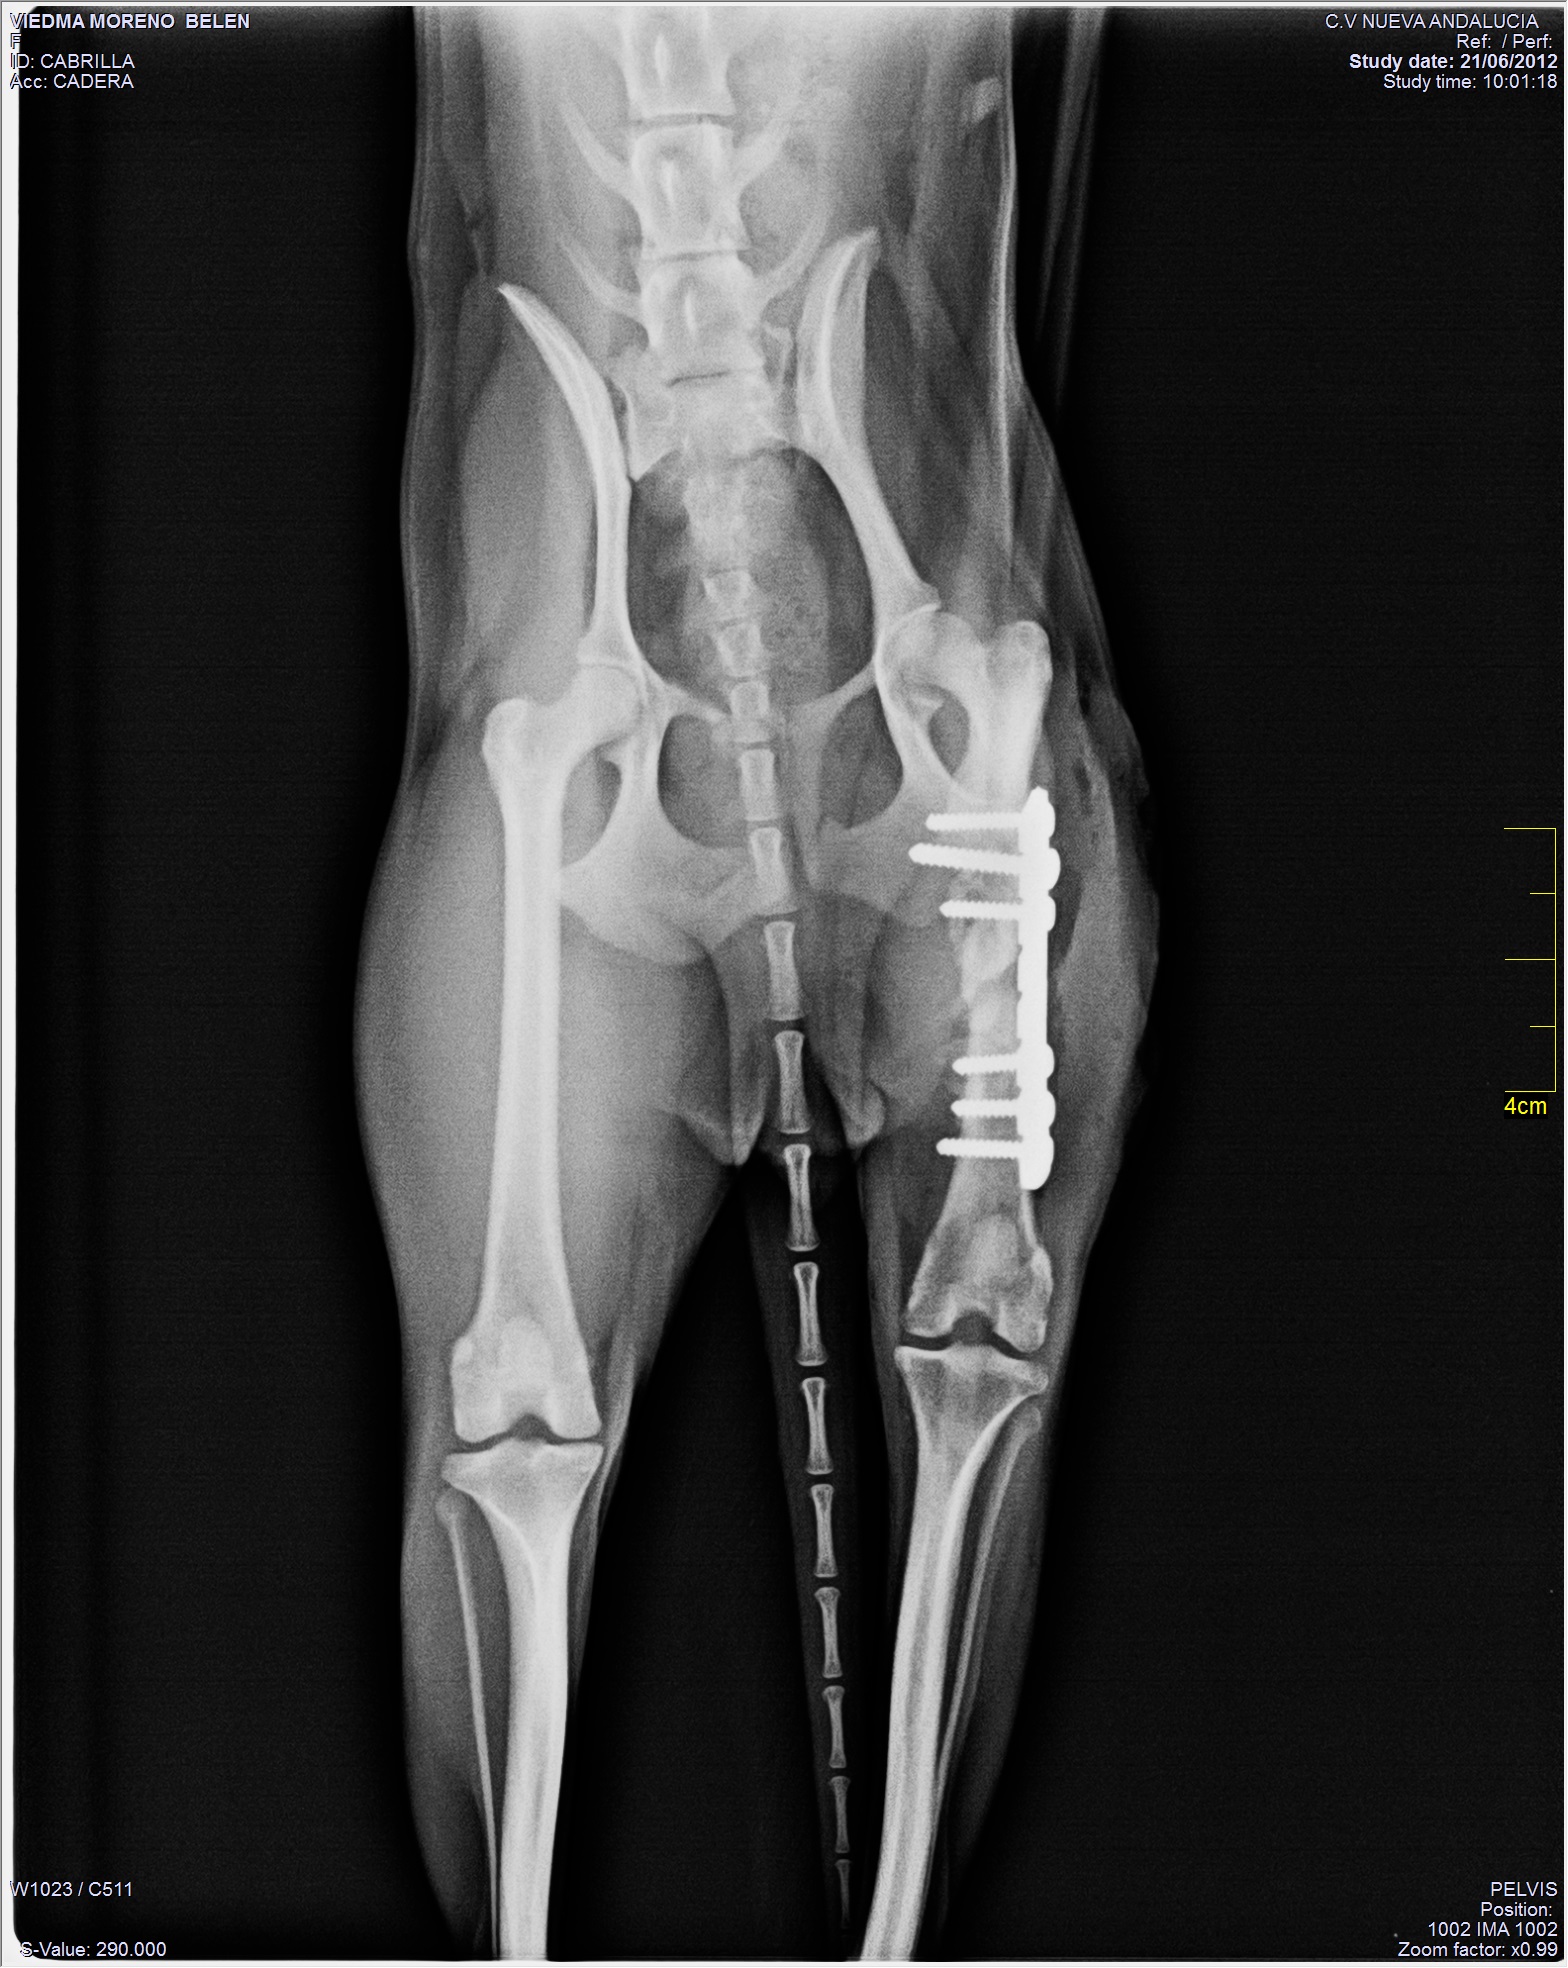

Atención Veterinaria de Emergencia Integral